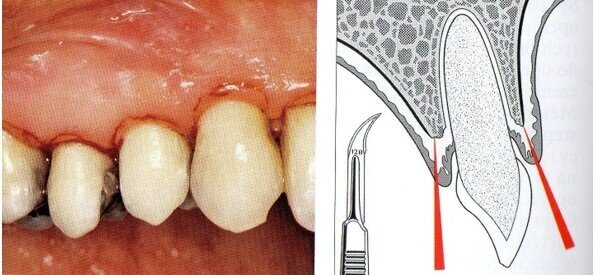

Badaniem wewnątrzustnym stwierdzono kieszenie o głębokości ponad 4 mm, wydzielinę ropną i krwawą, wskaźniki higieny wynosiły odpowiednio: API 25%, SBI 20%, wszystkie zęby w żuchwie wykazywały 3. stopień rozchwiania (Ryc. 1).

Dn. 18.09.2013 r. w znieczuleniu przewodowym zostały usunięte wszystkie zęby. Celem dokładnego usunięcia ziarniny przed ekstrakcją wykonano ucięcie wg Widmanna (Ryc. 3). Jednym z warunków powodzenia zabiegu jest dokładne usunięcie zmienionych chorobowo tkanek miękkich tak, by pozostawić zdrowe.